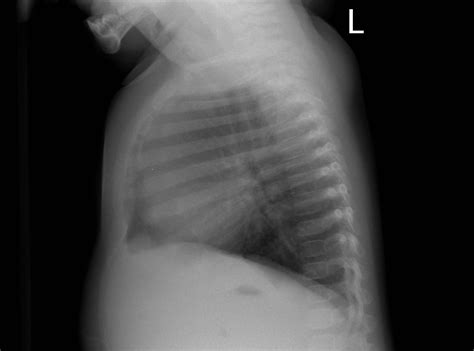

• Image Capture: Multiple images may be taken from different angles to provide a comprehensive view of the chest cavity.

Common Findings in a Normal Chest Ray

A Normal Chest Ray typically reveals the following structures and conditions:

Structure/Condition Description

Lungs Clear lung fields with no signs of infection, inflammation, or tumors.

Heart Normal size and shape, with no signs of enlargement or fluid accumulation.

Ribs and Spine Intact bones with no fractures or abnormalities.

Diaphragm Normal position and movement.

Pleural Space No fluid or air accumulation.